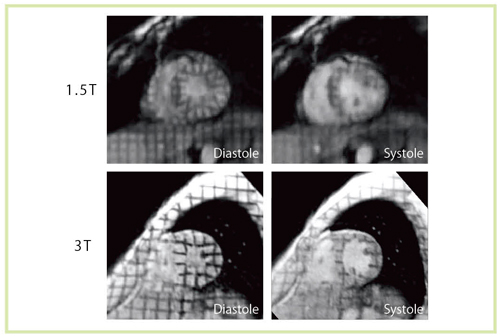

図12 1.5Tと3Tでのtagging法の比較 T1緩和時間の延長により,tagging標識が長時間持続する。

図12 1.5Tと3Tでのtagging法の比較

T1緩和時間の延長により,tagging標識が長時間持続する。